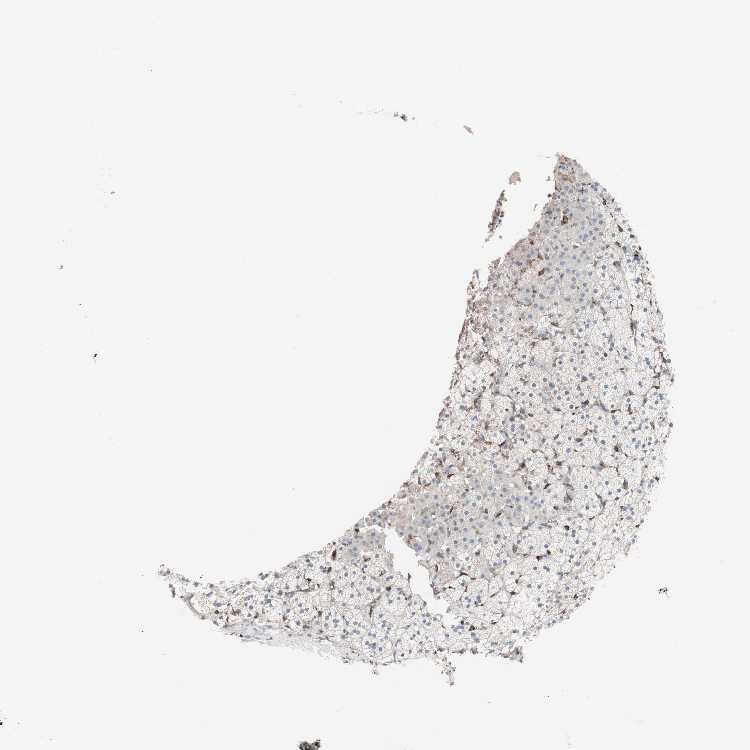

ADRENAL GLAND - Antibody stainingi

Antibody staining in the annotated cell types in the current human tissue is reported as not detected, low, medium, or high, based on conventional immunohistochemistry profiling in selected tissues. This score is based on the combination of the staining intensity and fraction of stained cells.

Each image is clickable and will lead to virtual microscopy that enables deeper exploration of all samples and also displays staining intensity scores, fraction scores and subcellular localization as well as patient and tissue information for each sample.

Antibody HPA007293Antibody CAB009771

Glandular cells LowHigh